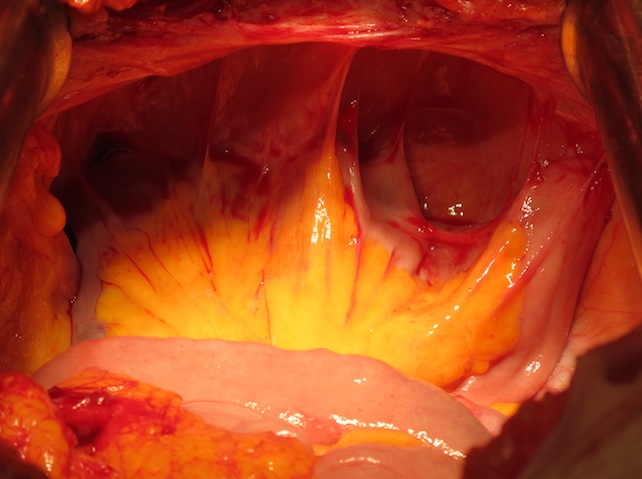

27.03.2013г. – операция: комбинированная надлеваторная эвисцерация малого таза с резекцией петли тонкой кишки: под эндотрахеальным наркозом выполнена нижняя срединная лапаротомия по старому послеоперационному рубцу. Малый таз выполнен опухолевым конгломератом, включающим культю влагалища, мочевой пузырь, прямую кишку и петли подвздошной кишки. Признаков отдаленного метастазования не выявлено.